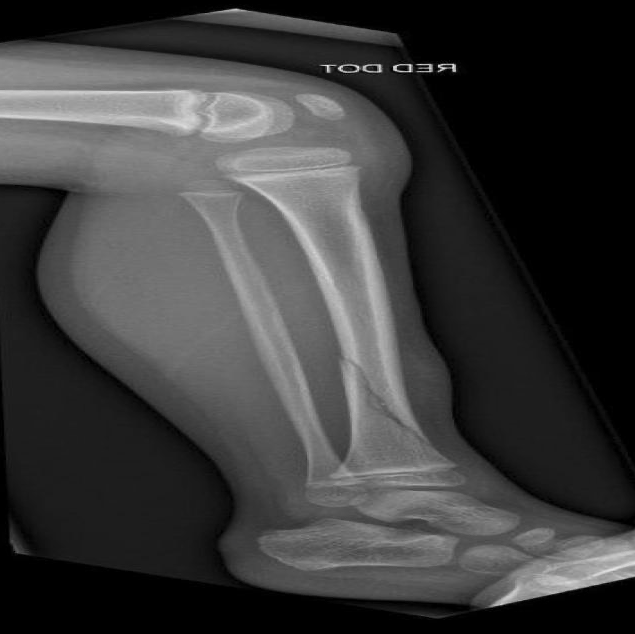

HBFMID, the full name of which is Human Bone Fractures Multi-modal Image Dataset, is a medical imaging dataset released by the American International University, Bangladesh in 2024. It aims to provide support for fracture detection and classification tasks. The dataset contains X-rays and MRI images of the elbow, fingers, forearm, humerus, shoulder, femur, tibia, knee, hip, wrist, spine, and some healthy bones. The dataset initially collected 641 original images (510 X-rays and 131 MRI images) and divided them into a training set of 449, a validation set of 128, and a test set of 64. All images were automatically oriented, resized (640×640), and contrast enhanced. Based on the training set, enhancement methods such as flipping, rotation, scaling, shearing, and brightness and saturation changes were further applied to generate approximately 1,347 augmented samples. The final dataset contains 1,539 images. This dataset integrates multimodal images, covers multiple parts, and has various display forms. It is fully enhanced and clearly divided. It is suitable for training and evaluating fracture detection and classification models, and is especially valuable in medical image analysis and deep learning research.